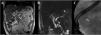

A y B) Colangiorresonancia magnética que muestra dilatación del conducto pancreático principal de hasta 8mm, con un trayecto serpiginoso y con disminución abrupta del calibre a nivel de la cabeza asociada a una imagen hipointensa intraluminal (flecha). C) Fluoroscopia en donde se observa un lito radiopaco en topografía de cabeza de páncreas (flecha).

Presentamos el caso de un varón de 58 años de edad con pancreatitis crónica quien ha presentado dolor abdominal persistente y cuadros recurrentes de pancreatitis aguda desde hace varios años. Tiene el antecedente de colecistectomía laparoscópica y niega historia de consumo de alcohol importante. En su último cuadro de pancreatitis aguda, se realizó una tomografía computada de abdomen en la que se reportó un lito localizado aparentemente en colédoco intrapancreático. Fue referido a nuestro hospital para la realización de una colangiopancreatografía retrógrada endoscópica (CPRE). Se complementó abordaje con una colangiorresonancia magnética en la cual se observó que la imagen correspondiente al lito se encontraba en realidad en el conducto pancreático principal a nivel de la cabeza y con dilatación de dicho conducto (fig. 1 A y B). Se decidió llevar a cabo manejo con CPRE convencional para extraer el lito pancreático. Después de lograr canular el conducto pancreático, se avanzó una guía 0.035” hasta topar con un lito radiopaco de 7mm que no permitió mayor avance, por lo que no fue posible completar el procedimiento planeado (fig. 1C). Se realizó esfinterotomía y se colocó una prótesis plástica pancreática 5 Fr de manera temporal. Se realizó una segunda intervención en otro tiempo, que consistió en una CPRE junto con pancreatoscopia de un solo operador (Sistema SpyglassTM DS). Para facilitar la inserción del dispositivo, se realizó esfinteroplastia con balón de dilatación hidráulico de 8mm diámetro y 3cm de longitud con lo que se logró avanzar sobre el conducto pancreático principal. Una vez que se encontraba la sonda (AutolithTM Touch Biliary EHL System) a 1mm del lito, se realizó litotripsia electrohidráulica (configuración de energía 50 watts y frecuencia 10/seg.) hasta lograr fragmentarlo en pedazos muy pequeños que fueron removidos del conducto pancreático con balón extractor 9mm/12mm (fig. 2, video complementario: procedimiento acortado de CPRE y pancreatoscopia). Se colocó una prótesis plástica pancreática profiláctica 5 Fr x 7cm concluyendo de esta manera con el procedimiento. No se reportaron complicaciones asociadas al procedimiento. En su última consulta, el paciente no ha vuelto a referir dolor a cinco meses de la intervención.